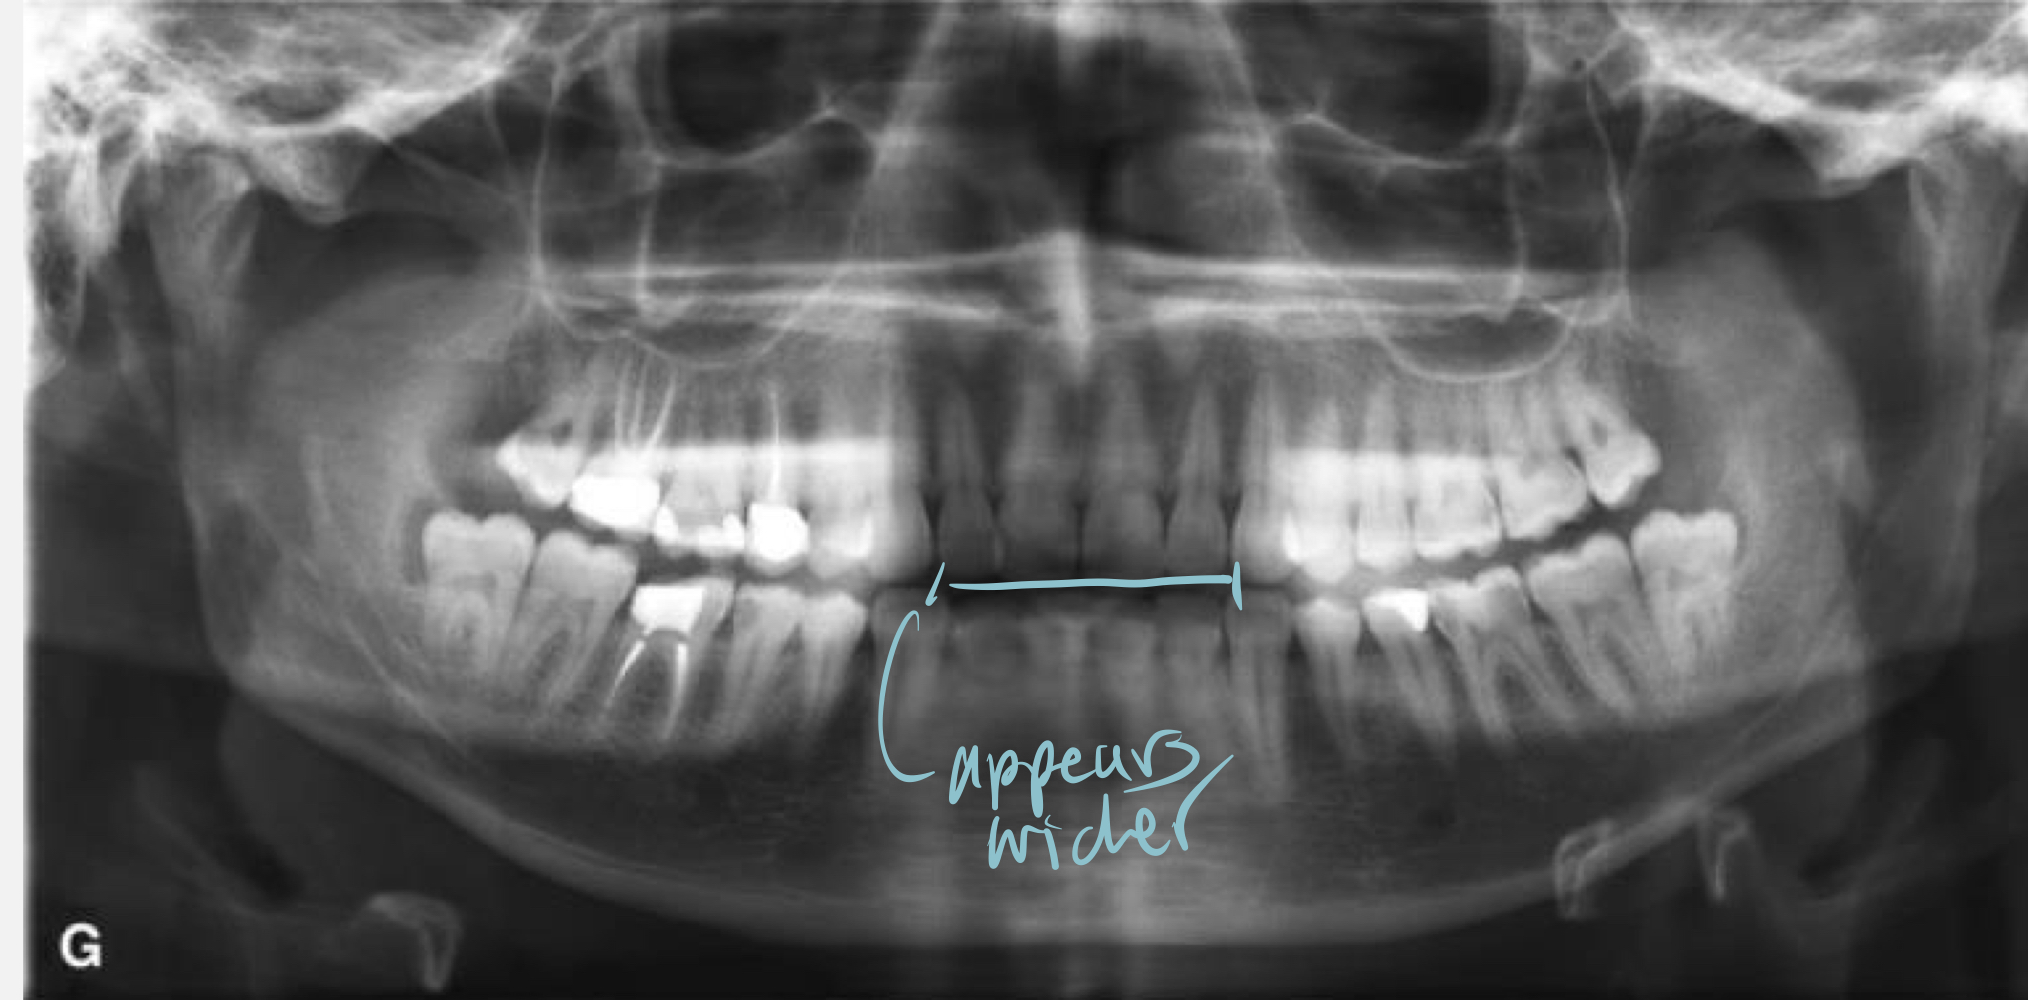

What happens when the mandible is at the center of the focal trough?

Minimal distortion of image

What happens if the mandible is posterior to focal trough?

Widening of image

What happens if the mandible is anterior (too front) to the focal trough?

Lengthening of image